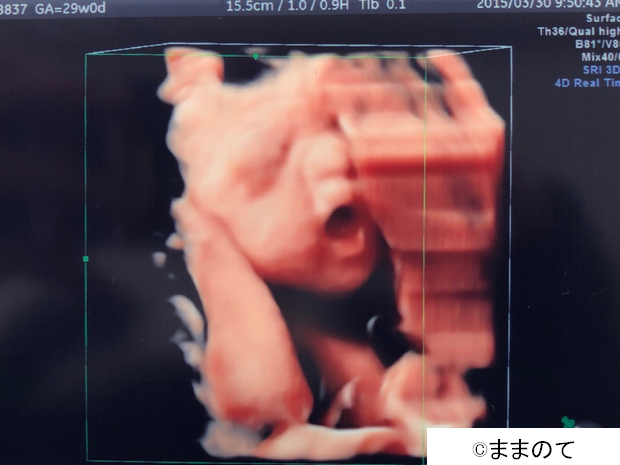

「ママ似かもしれないね」

左は妊娠24週の4Dエコー画像、右は出産直後の写真です。ママとパパは4Dエコーを見たときに「ママ似かな?」と思い、実際に生まれた男の子の顔を見て「やっぱりママに似ていたね」と言い合ったのだとか。しかし、成長するにつれてどんどんパパに似てきているそうです。